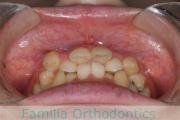

No.23V-478

- 叢生

- 30歳

- 男性

- 抜歯部位

- 上:

- 44済

- 下:

- 8558済

- 主な使用装置:

- FEA 022

- 治療にかかった費用:

- 76万円

右上の歯が重なっているところが邪魔になるとのことで矯正治療を始められた患者さんで、札幌から転院されました。当院で約1年半、15回程度の通院が必要でした。叢生(でこぼこ、凹凸、ガタガタ)が強く、後戻りのリスクが高いケースです。